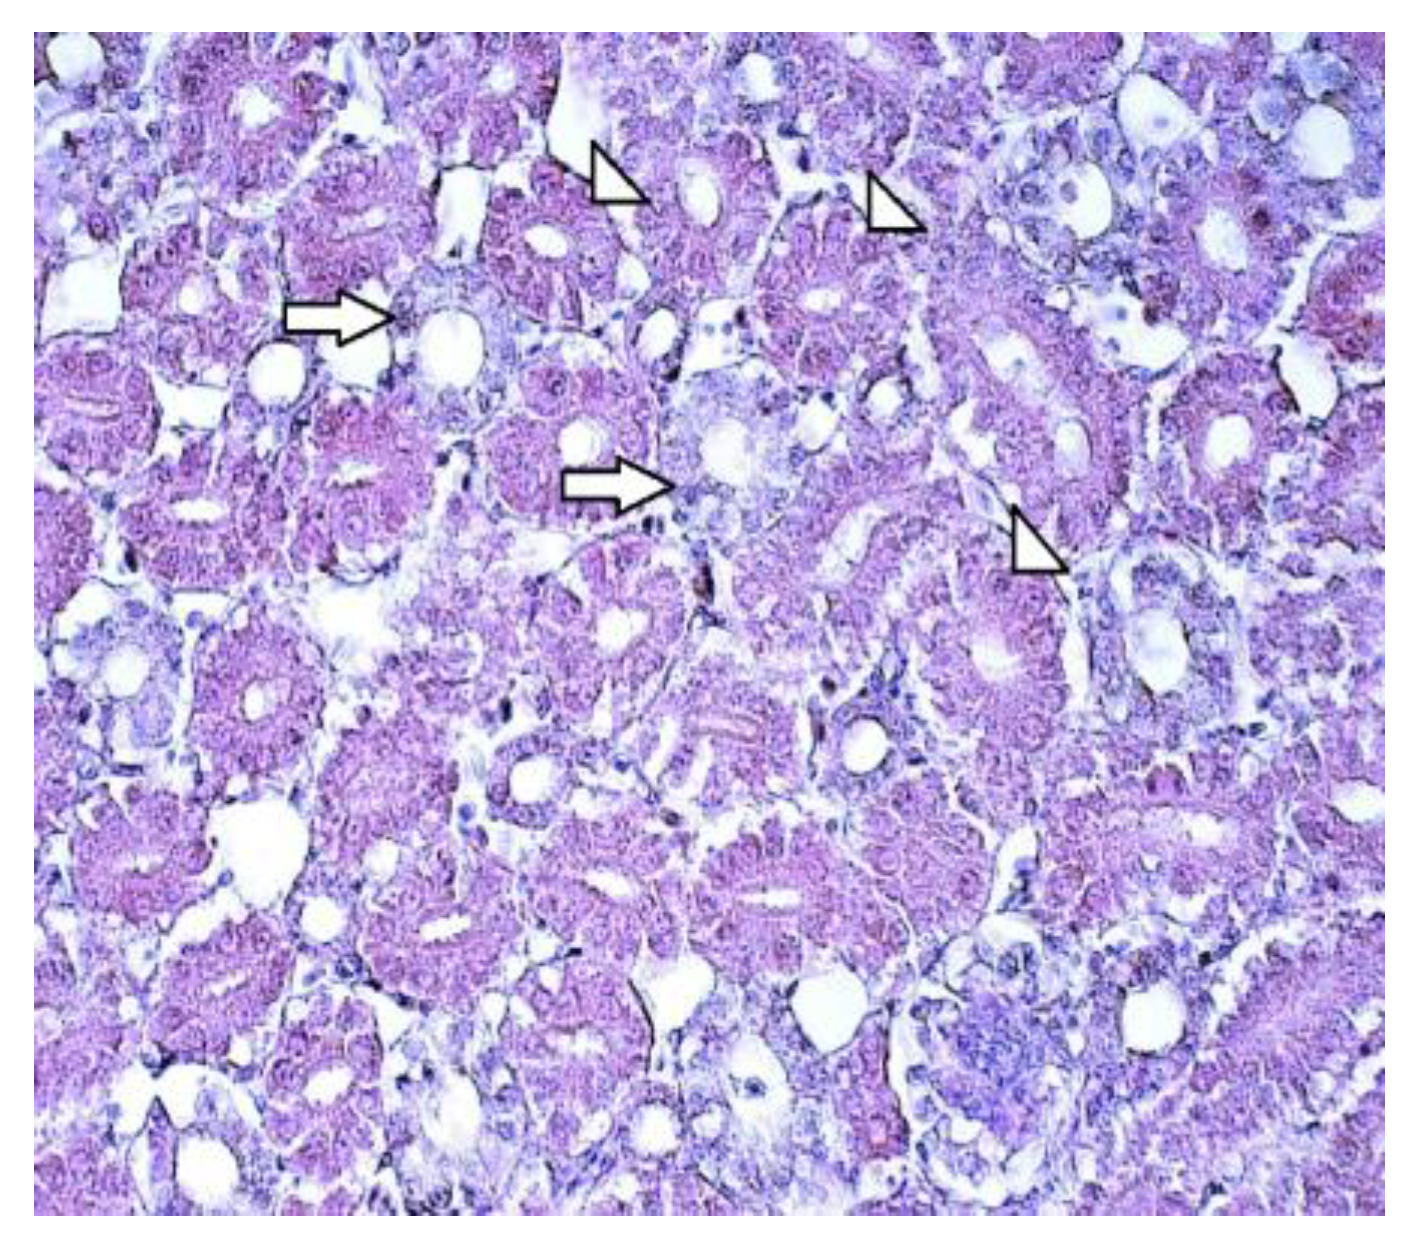

3.1. Routine Histology